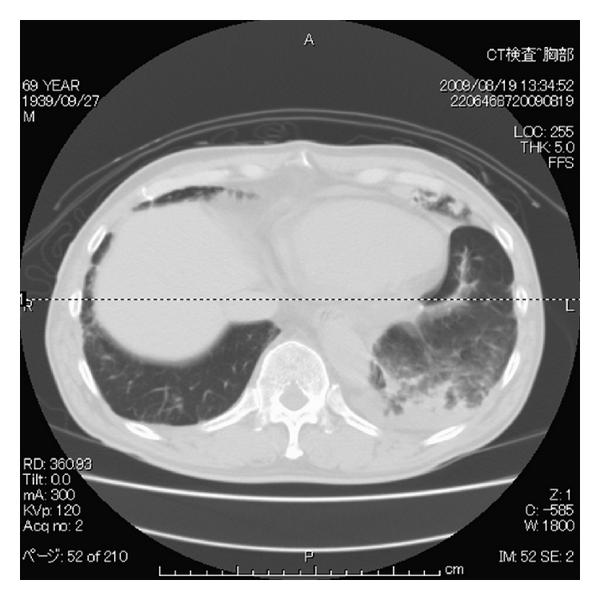

Initial PTPA was performed for his left pulmonary artery. Seven peripheral regions of his left pulmonary artery was dilated by the balloon. At the end of the procedure, his pulmonary artery pressure was 91/27 mmHg, and he was admitted to the intensive care unit. On admission to the intensive care unit (day 0), his SpO2 was 95% with 40% of oxygen inhalation with no complain of dyspnea. On day 1, his chest X-ray and computed tomography revealed localized consolidation on his left lower lobe (Figure 1). On day 2, consolidation on chest X-ray developed in accordance with his complication of dyspnea. Because his SpO2 decreased to 70% with 10 L/min of oxygen inhalation using reservoir mask, NPPV was applied.

(a)

(b)